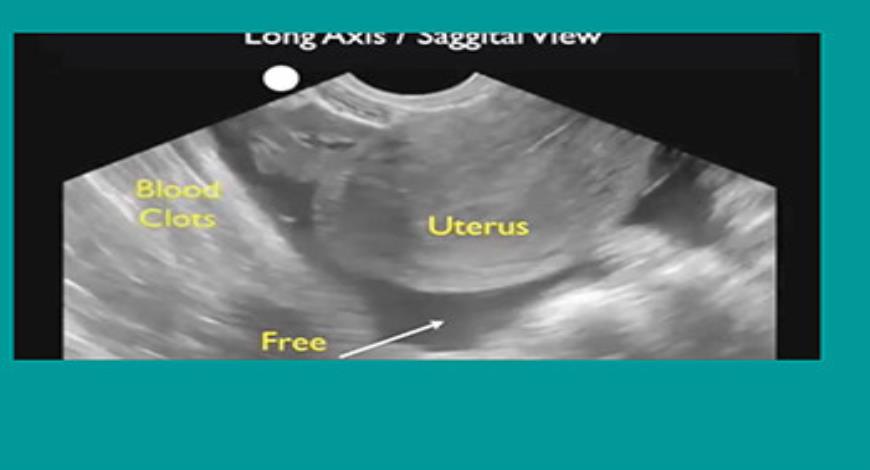

Ectopic Pregnancy Nursing Care And Management

Ectopic Pregnancy Nursing Care and Management nurseslabs.com

pregnancy ectopic nurseslabs